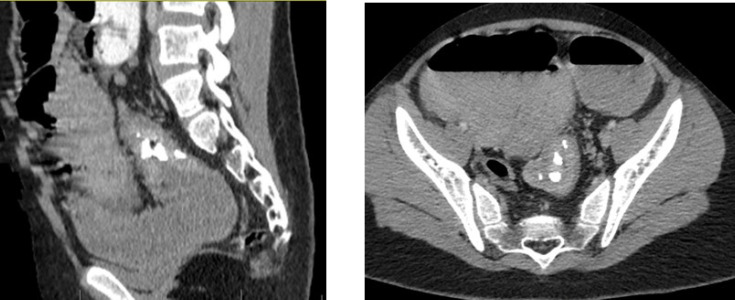

The occurrence of rectosigmoid junction inflammatory myofibroblastic tumor (IMT) is uncommon in children. This is a rare form of mesenchymal tumor, belonging to the category of soft tissue tumors, and can be found at any anatomical site from the central nervous system to the gastrointestinal tract. Our patient was a 10-year-old male subject complaining of lack of defecation and constipation. The patient had decreased the frequency of defecation and constipation about two weeks before his referral and had not improved despite the use of laxatives. The abdomen was completely distended and there was no tenderness or guarding in the examination. Several airfluid levels are shown on the abdominal X-ray. In the ultrasound, free fluid was reported in the interlobular and pelvic spaces. The patient was transferred into the operating room. A tumor of the rectosigmoid junction was detected. Histopathologic studies showed evidence of IMT. IMT is a rare neoplasm of unknown origin, which may occur in various sites of the body. Complete surgical removal is usually curative, but early detection of recurrence is required. Treatment options include chemotherapy, radiation therapy, and immunotherapy. Further investigations are needed to improve the understanding and management of this rare tumor.